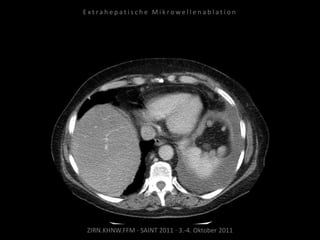

Kontrolle:

CT 08.10.2010

CT 05.11.2010

Kein Progress im abladierten Areal.

Erfolgreiche Schmerztherapie.

CT 03.12.2010

CT 03.05.2011

Resultat:

Kein weiteres Tumorwachstum im

abladierten Areal. Schmerzsymptomatik

deutlich gebessert.

Fazit:

Die MWA ist außerhalb eines kurativen

Ansatzes geeignet, Tumorwachstum zu

bremsen und Symptomatik zu

vermindern.